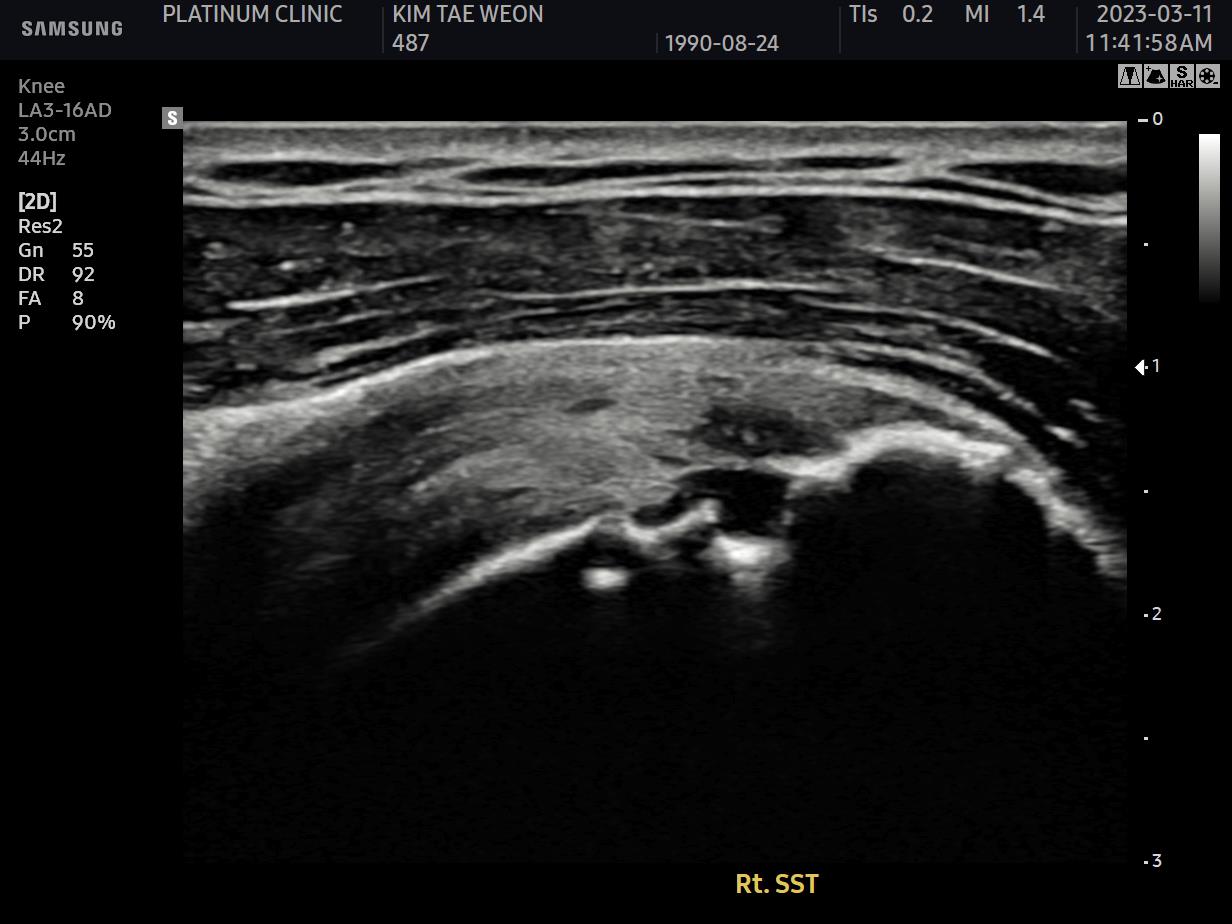

저는 먼저 이학적검사를 시행했습니다. 환자분의 어깨를 직접 만지고, 여러 방향으로 움직여보며 통증이 발생하는 지점과 각도를 확인했습니다. 그리고 초음파 검사를 진행했습니다.

MRI 영상에서는 큰 이상이 보이지 않았습니다. 그런데 초음파로 어깨를 움직이면서 검사하니, 회전근개가 결대로 세로로 찢어진 형태의 파열이 확인되었습니다. 팔을 움직일 때마다 찢어진 인대 섬유가 갈래갈래 벌어지면서 통증과 염증을 유발하고 있었던 것입니다.

초음파 검사: 움직이면서 인대를 봅니다

- ✓인대(회전근개)의 손상 여부

- ✓인대 파열의 위치와 정도

- ✓연부조직의 염증 정도

초음파의 가장 큰 장점은 실제로 어깨를 움직이면서 검사할 수 있다는 점입니다.